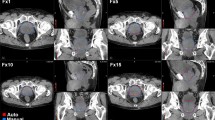

Fifty patients enrolled in institutional review board (IRB)-approved protocols for the treatment of PCa were selected for this study. The ethical approval for this study was obtained from the University of Miami Institutional Review Board (IRB). Written informed consent was obtained from all patients in this study. The data was retrospectively collected and analyzed. All methods undertaken in this work were carried out in accordance with the relevant guidelines and regulations. Characteristics of the patient cohort are summarized in Supplementary Table S1. To maintain consistency in imaging quality and reduce variability between different kV imaging devices available in the facility several constraints were placed on the patients selected for this study. Only PCa patients who received definitive volumetric modulated radiation therapy (VMAT) on a TrueBeam linear accelerator (Varian Medical Systems, Palo Alto, CA) with daily CBCT were included in the study. Raw projection data was exported from the treatment machines and later reconstructed using image reconstruction software to maintain consistent reconstruction parameters for all the images. More details on image reconstruction are described in the following section. Patients with body mass index (BMI) > 40 or intrapelvic metal prostheses were excluded due to X-ray hyper attenuation and metal streaking artifacts, respectively. CBCT images were analyzed from the daily scans throughout the entire course of treatment.

All clinical CBCT images used in this study had the same image size (512 × 512 pixels), pixel size (0.9 mm), slice thickness (2 mm), and FOV (465 mm). The tube voltage (125 kVp) and tube current–time product (1073–1074 mAs) were consistent for all CBCT scans.

sCBCT refers to CBCT images reconstructed using standard filtered back-projection reconstruction. iCBCT refers to CBCT images reconstructed using an iterative reconstruction algorithm that employs a scatter correction method that estimates scatter in X-ray projection images by solving the linear Boltzmann transport equation and statistical iterative reconstruction for final-pass image reconstruction30. For all patients, raw projections of both sCBCT and iCBCT images were collected to reconstruct CBCT images using the reconstruction method of choice (sCBCT or iCBCT) post-treatment. A research image reconstruction software (iTools, Varian Medical Systems, Palo Alto, CA, USA) was used to generate either sCBCT or iCBCT image sets for each patient. Daily CBCT raw projections were reconstructed utilizing eight combinations of various reconstruction algorithms, convolution filters, and noise suppression filters (Table 1). One aim of the iterative reconstruction algorithm is to minimize the variation in voxel intensity in the final reconstruction. The degree to which this variation is minimized is referred to as the noise suppression. While noise suppression is only available in iCBCT, different convolution filters can be applied to both iCBCT and sCBCT. Convolution filters can affect image spatial frequency characteristics by convolving the image with a kernel. Though the aim of convolution filters and noise suppression is to improve image quality in one way or another, there are tradeoffs. Smooth convolution filters can reduce noise at a loss of resolution. Very high noise suppression will reduce noise at a loss of contrast. Delgadillo et al. analyzed the repeatability and reproducibility of CBCT-based radiomic features for PCa patients receiving RT31 and found that reconstruction and preprocessing parameters that improve feature repeatability often decrease reproducibility31. Reconstruction and preprocessing paraments that strike a balance between repeatability and reproducibility are recommended. Considering tradeoffs between image filters and image quality and the findings from Delgadillo et al.31, CBCT images in this study were reconstructed using Very Low noise suppression, when applicable, and Sharp convolution filter. Since CT has higher image quality and has been shown to be useful for modeling and predicting outcome25, it would be useful if some predictive feature were reproducible to daily CBCT to exploit changes during treatment that are predictive to patient outcome. However, the reconstruction parameters used in the clinic are typically Medium noise suppression, when applicable, and standard convolution filter. The default clinical image reconstruction settings were also included to compare the delta-radiomics feature model performance for CBCT with reconstruction parameters more typically used in other clinics. An example of a reconstructed prostate CBCT image using the different reconstruction parameters considered in this work is shown in Supplementary Fig. 1.

Prostate contours